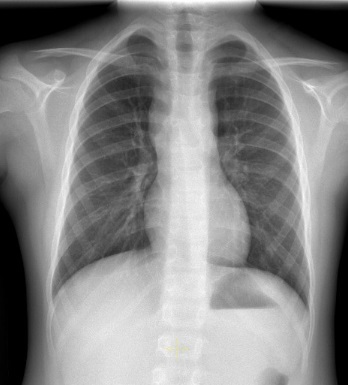

Ante empeoramiento clínico progresivo se repite estudio de nuevo. Analítica de sangre con discreta elevación de LDH y hemograma sin citopenias. En la radiografía de tórax se observa engrosamiento de la banda paratraqueal derecha con ensanchamiento mediastínico bilateral (Fig. 1). En la ecografía de cuello se evidencia la presencia de adenopatías patológicas, aumentadas de tamaño con pérdida del hilio graso.

Figura 1. Ensanchamiento mediastínico bilateral

Figura 1. Ensanchamiento mediastínico bilateral.